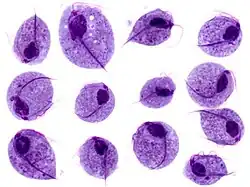

| Trichomonas-trofozoïten | ||||||||

Trichomonas is een geslacht van protista. Besmetting met Trichomonas vaginalis wordt ook wel kortweg trichomonas genoemd in plaats van trichomoniasis. Wereldwijd is trichomonas de meest voorkomende niet-virale geslachtsziekte. In Nederland worden zo'n 2000 besmettingen per jaar geconstateerd.

Bij onderzoek van het uitstrijkje (cervixcytologie) is de Trichomas vaginalis de meest voorkomende parasiet. De incubatietijd van trichomonas ligt tussen de 4 en 28 dagen. Hij kan abnormale vaginale afscheiding (fluor vaginalis) veroorzaken maar is niet altijd pathogeen.

In ongeveer 10-20% geeft hij een infectie van de lagere urinewegen, gepaard met dysurie. Bij 10-25% van de patiënten zien we een vies ruikende groengele, schuimige vaginale afscheiding, vaginale jeuk en vaginaal bloedverlies. Symptomen als PID (Pelvic Inflammatory Disease)en inguinale lymphadenopathie (vergrote lymfeklieren) kunnen voorkomen.

Behandeling geschiedt meestal met antibiotica (metronidazol of clindamycine).